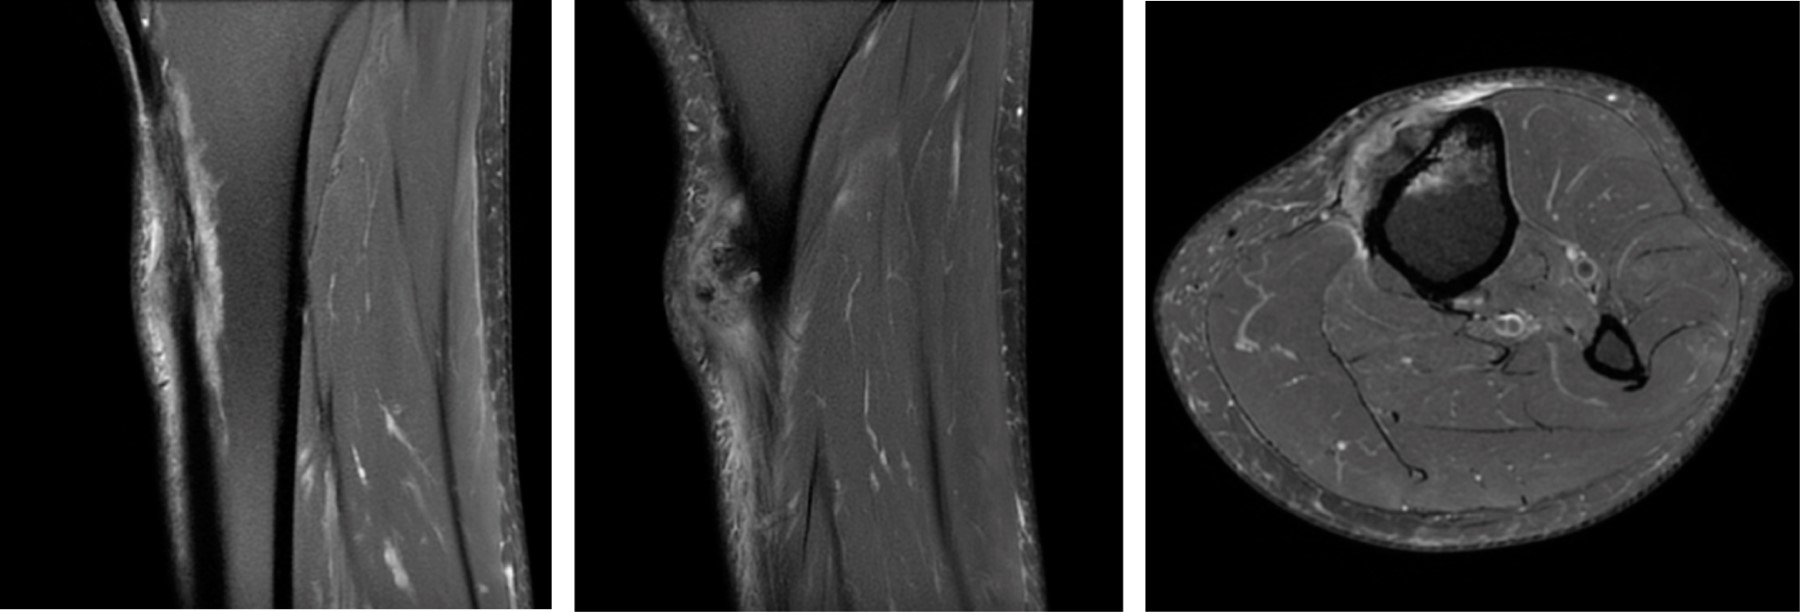

Initially a XR, CT and MR were performed showing a soft tissue tumor on the proximal aspect of the left tibia just inferior to the tibial tuberosity, size of 40 × 29 × 19 mm (coronal × sagittal × axial). Emerging from the anterior tibia periosteum and growing towards the subcutaneous tissue, hyperintense in T2 and hypointense in T1. Tumor presents with irregular and extensive internal calcifications (Figure 2). An initial biopsy was performed that was inconclusive, so an ultrasound guided biopsy was done afterwards with a 14G needle. The pathologist could not conclude between, hypertrophic fracture callus, osteoblastoma or osteosarcoma subtype osteoblastoma.

Three months later MR was repeated showing increase in size 42 × 40 × 27 mm and small areas of necrosis. Large attachment to the anterior periosteum remains with exophytic growth contacting the skin (Figure 3). With new imaging a third biopsy was performed guided with ultrasound. It showed trabecular osteoid areas that converge and areas of spindle cells with moderate cellular atypia, that suggested cPOS or HGSO.